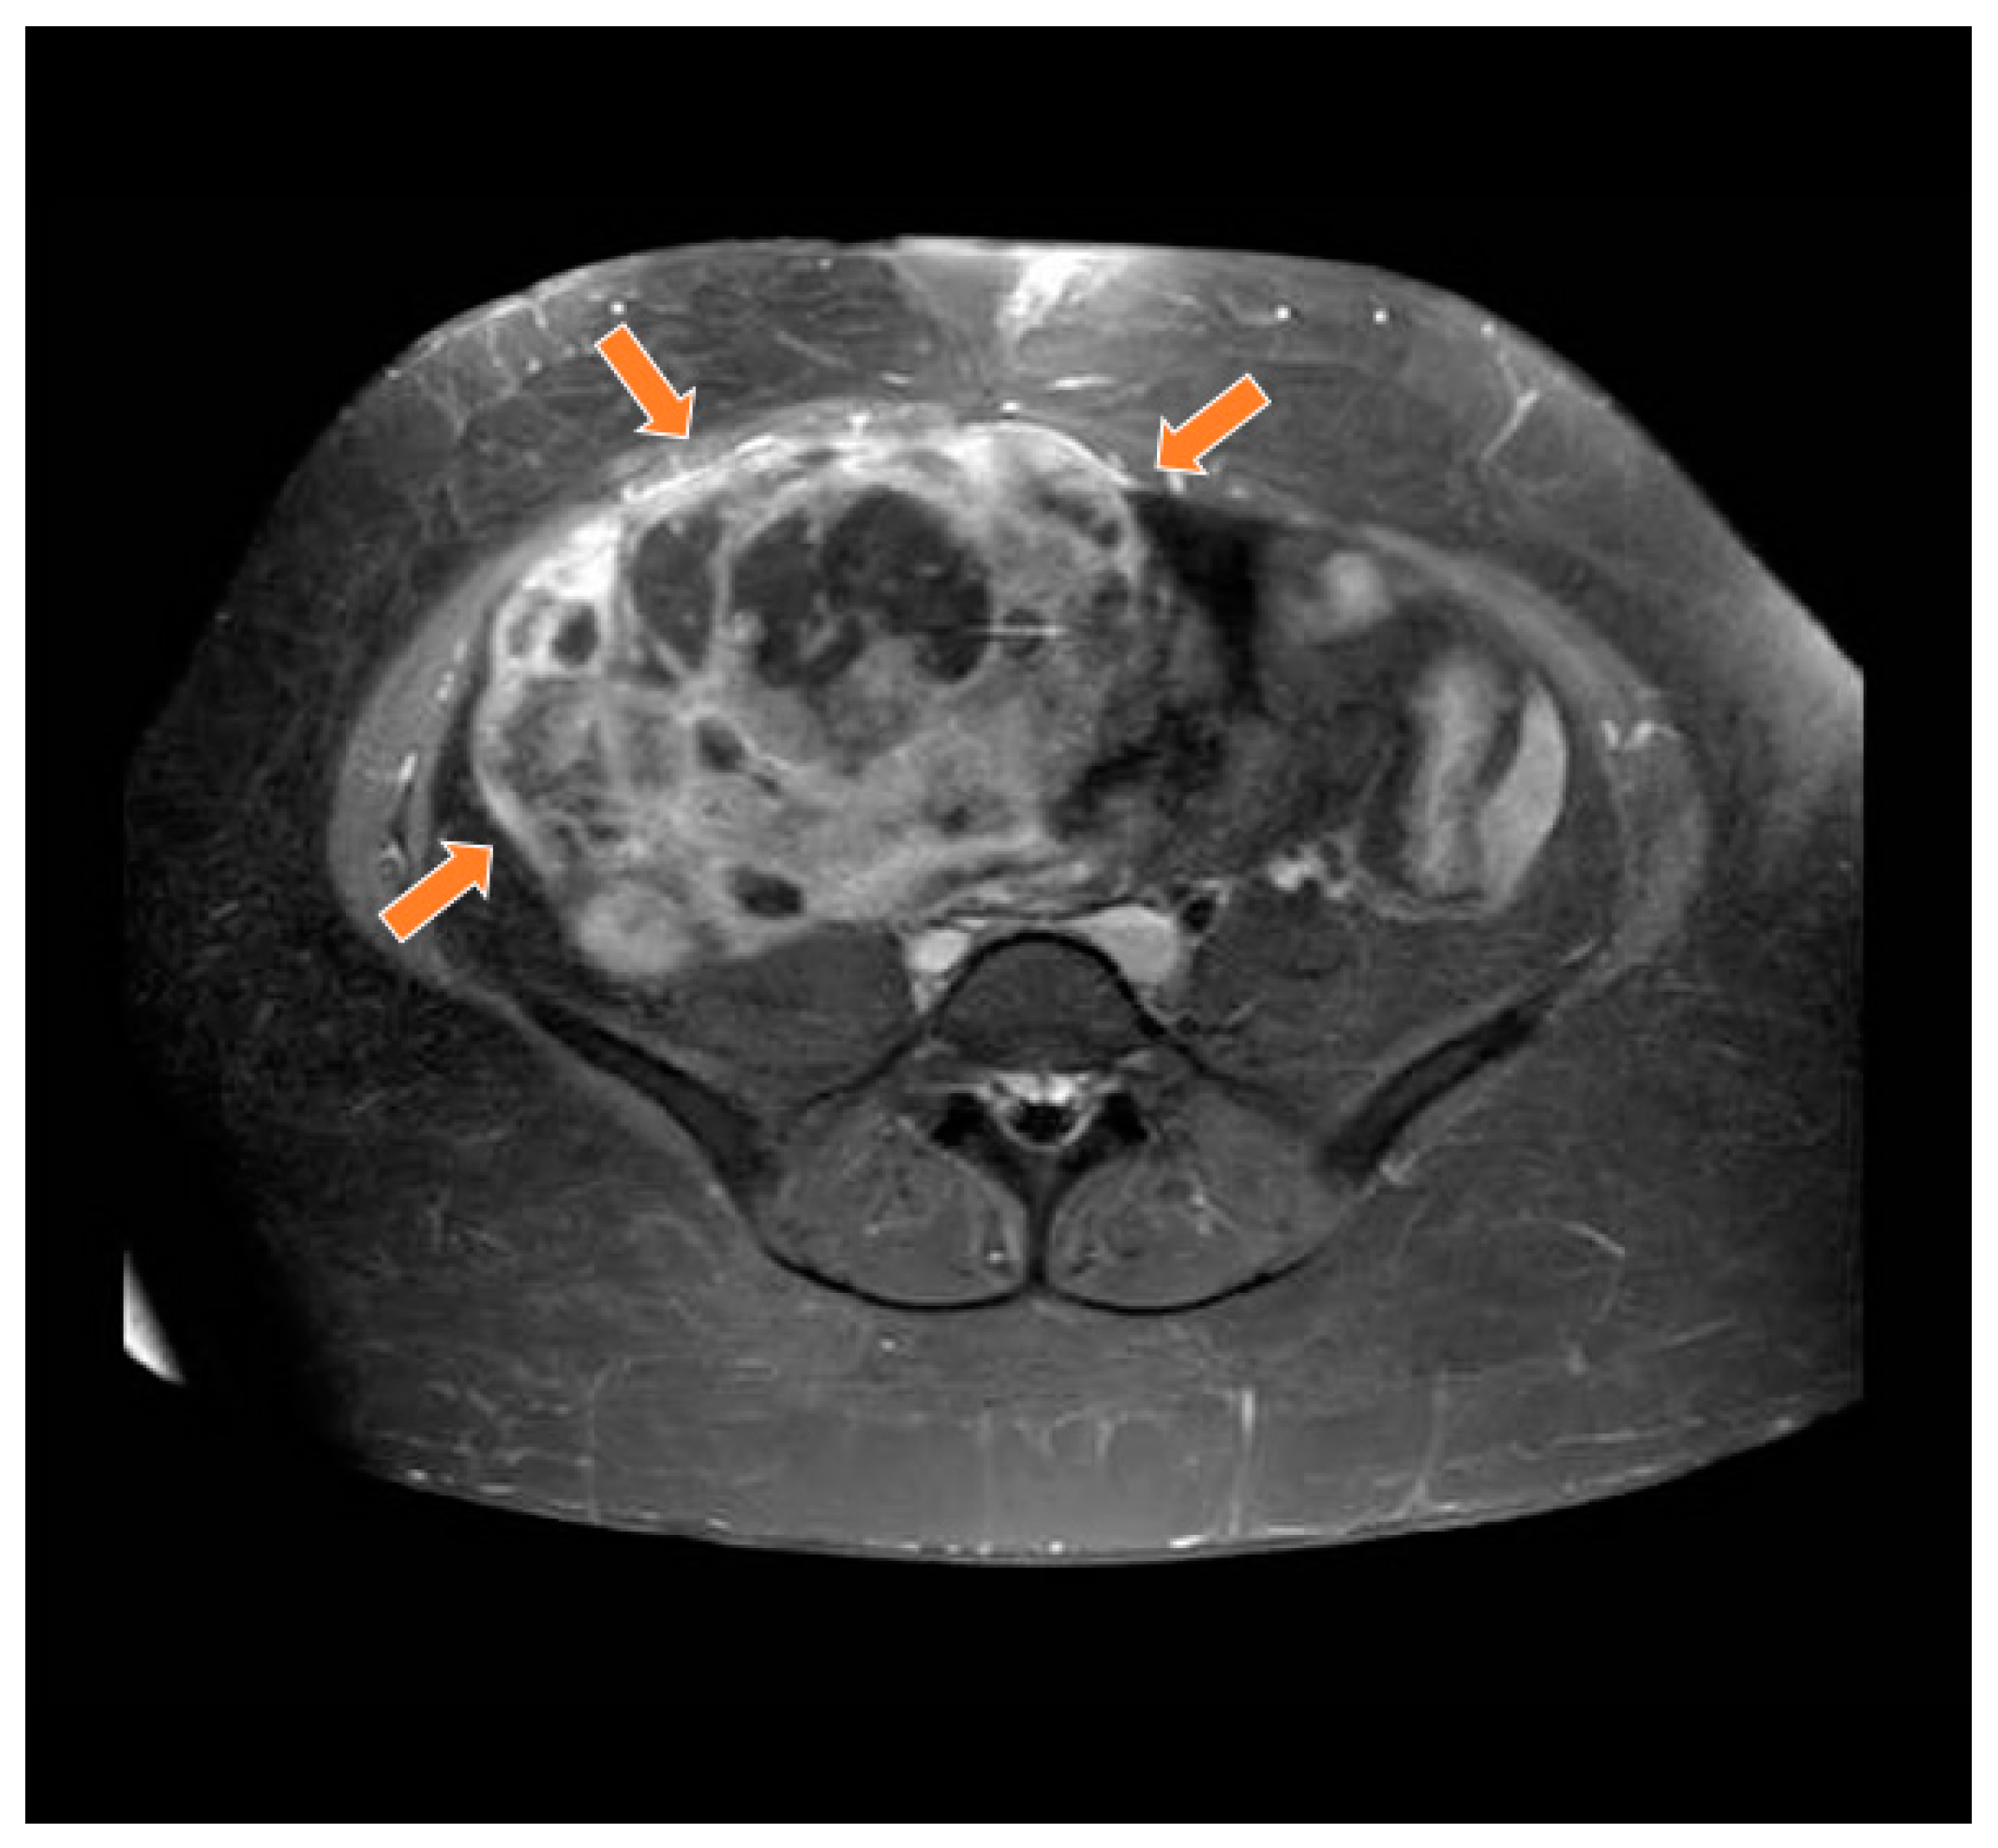

Figure 2.

Magnetic resonance study in T1 weighted sequence post gadolinium showing a heterogeneous mass in the pelvic region (orange arrows).